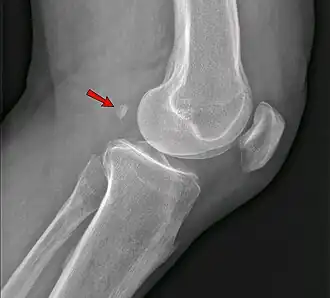

Knee

• The fabella is present in 10% to 30% of individuals.[1]

The fabella is present in 10% to 30% of individuals.[1]